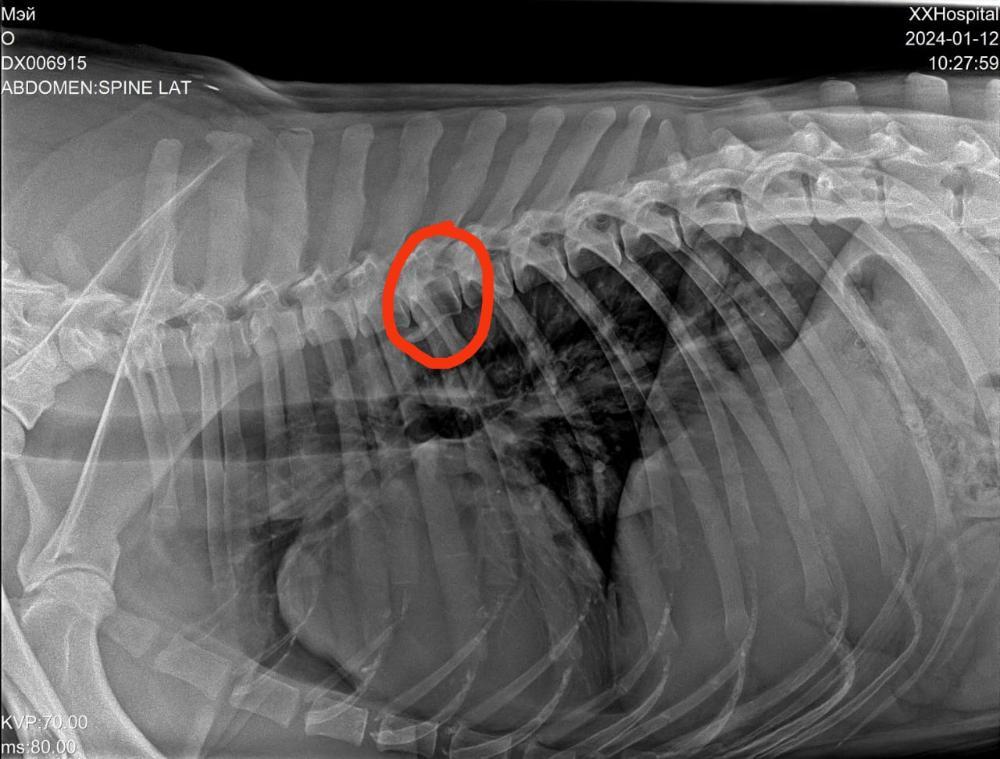

Светлана 2101 Опубликовано 12 января, 2024 Опубликовано 12 января, 2024 Сегодня съездили с Мэем к ортопеду. Сделали рентген. Сразу скажу, я осталась очень довольна приемом, содержательной беседой с врачом. Но есть новости хорошие и не очень. Сделано - рентген грудной и поясничный отдел, тазобедренных суставов и рентген оперированной лапы. По позвоночнику - в прекрасном состоянии, нет признаков травмы и дегенеративных изменений, кроме единичного незначимого очага дискоспондилита в среднем грудном отделе. На одном позвонке только есть изменения ( на снимке красным). Это ни о чем .Никак на жизнь не влияет. Тазобедренные суставы в отличном состоянии, без признаков дисплазии. В оперированной лапе - конструкция стабильна, признаки консолидации отломков. То есть всё хорошо. Доктор сказал, что далее ещё больше укрепляться будет. Процесс нарастания костной мозоли ещё идёт. Новости не очень. Измерил угол наклона плато, это крепление связок. Не очень владею всеми терминами, но своими словами напишу, как поняла. Этот угол у Мэя 20°, норма 14, при значении 25 и выше сто процентов разрыв ПКС неминуем. Хоть доктор и написал в заключении, что риск разрыва ПКС невелик, но на словах мне сказал, что вероятнее всего рано или поздно связки порвутся. 20° это уже большое натяжение, рвутся и при 22-23. Соответственно, рекомендации режим спокойных прогулок в монорежиме без кучных игр для минимизации нагрузки на коленные суставы . То есть спокойный режим даже не столько для оперированной лапы, сколько угроза разрыва ПКС. По словам доктора, это генетическая предрасположенность. В беседе он так сказал, что, да вы можете стараться его ограничивать от прыжков, но один раз он не прыгнет, а в другой раз всё равно прыгнет. Теперь вы знаете, что можно ожидать, но совсем собаку не ограничить во всем. А Мэй как раз очень прыгучий. Он даже на подзыв не просто подбегает, а прыгает.И бежит он прыжками. Один плюс, что он не знает диванов, и нет этого туда-сюда по 20 раз в день. Но на улице он хочет бегать. И бегает он очень мощно.Теперь понятно, что надо помнить об этом и стараться минимизировать прыжки . Но до сих пор связки целы, а прожил он с ними уже несколько лет, и режим у него был наверняка активный, никто его не ограничивал. Есть надежда, что продержатся они и ещё. И опять здесь очень хорошо, что он на НП, натуральные коллагены и Хондроитины помогут укреплению связок и сохранят суставы и позвоночник ,которые сейчас в прекрасном состоянии . Вот такое обследование. Я очень рада, что нет проблем в позвоночнике и суставах. Но не без ложки дегтя. Всё равно спокойный режим прогулок и жизни. А там как сложится. Просто теперь мы об этом знаем, что можно ожидать . 4 3

Светлана 2101 Опубликовано 12 января, 2024 Опубликовано 12 января, 2024 Рентген грудного отдела, вот единственный позвонок с дискоспондилитом, остальные все красивые Рентген пояснично крестцового отдела. Без изменений. Рентген тазобедренные. Рентген конструкции на оперированной лапе и углы. 5